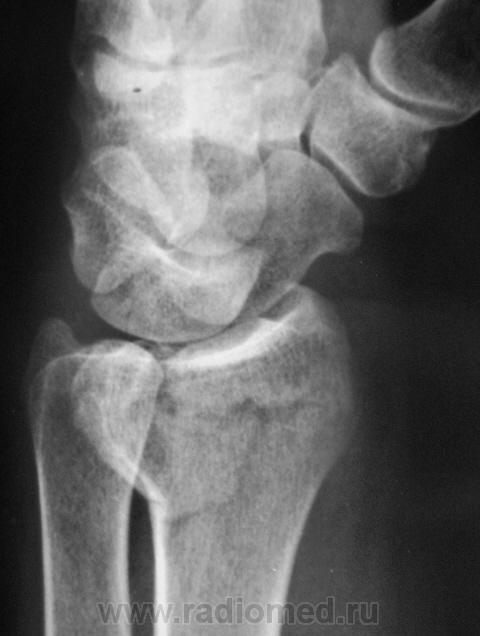

Катенёв Валенти... Дата публикации 12.01.2010, 17:50 Случай 1. Пациент направлен хирургом на рентгенографию лучезапястного сустава. Втр, 12/01/2010 - 18:02 #1 Катенёв Валенти... Не на сайте Был на сайте: 7 лет 3 недели назад Зарегистрирован: 22.03.2008 - 22:15 Публикации: 54876 Случай 2. Пациент направлен на рентгенографию лучезапястного сустава. Comment Upload: Втр, 12/01/2010 - 18:09 #2 Катенёв Валенти... Не на сайте Был на сайте: 7 лет 3 недели назад Зарегистрирован: 22.03.2008 - 22:15 Публикации: 54876 Случай 3. Пациент направлен на рентгенографию плечевого сустава. Comment Upload: Ср, 13/01/2010 - 17:31 #3 Ольга Дмитриевна Не на сайте Был на сайте: 15 лет 9 месяцев назад Зарегистрирован: 13.01.2010 - 16:55 Публикации: 168 По поводу случая 1. С лучом все понятно, а вот переломовывих ладьевидной кости? Как думаете? Красота - гормон карьерного роста! Ср, 13/01/2010 - 22:53 #4 Катенёв Валенти... Не на сайте Был на сайте: 7 лет 3 недели назад Зарегистрирован: 22.03.2008 - 22:15 Публикации: 54876 А вот как трактовать в случае 2 перелом? Ср, 13/01/2010 - 23:47 #5 Ольга Дмитриевна Не на сайте Был на сайте: 15 лет 9 месяцев назад Зарегистрирован: 13.01.2010 - 16:55 Публикации: 168 В случае 2 - на мой взгляд внутрисуставной перелом задненаружного края дист эпифиза лучевой кости. Что за +ткань по нар краю эпифиза луча - сложно сказать, мож ломал раньше. Красота - гормон карьерного роста! Ср, 13/01/2010 - 23:48 #6 Ольга Дмитриевна Не на сайте Был на сайте: 15 лет 9 месяцев назад Зарегистрирован: 13.01.2010 - 16:55 Публикации: 168 Что скажете по поводу случая1? Красота - гормон карьерного роста! Чт, 14/01/2010 - 18:17 #7 Глазков Игорь А... Не на сайте Был на сайте: 9 месяцев 2 недели назад Зарегистрирован: 19.12.2008 - 20:41 Публикации: 1597 оскольчатый перелом лучевой кости. Прийди к Себе Пт, 15/01/2010 - 22:26 #8 Катенёв Валенти... Не на сайте Был на сайте: 7 лет 3 недели назад Зарегистрирован: 22.03.2008 - 22:15 Публикации: 54876 "Красиво" упал. "Красивый" перелом Comment Upload: Вс, 17/01/2010 - 09:48 #9 Катенёв Валенти... Не на сайте Был на сайте: 7 лет 3 недели назад Зарегистрирован: 22.03.2008 - 22:15 Публикации: 54876 Случай 5. Comment Upload:

оскольчатый перелом лучевой кости.

"Красиво" упал. "Красивый" перелом